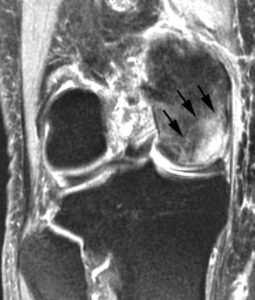

This MRI scan shows osteonecrosis in the medial femoral condyle. An MRI is often used to detect early symptoms of the disease.